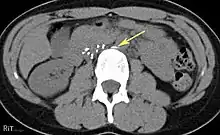

Placement

IVC filters are placed endovascularly, meaning that they are inserted via the blood vessels. Historically, IVC filters were placed surgically, but with modern filters that can be compressed into much thinner catheters, access to the venous system can be obtained via the femoral vein (the large vein in the groin), the internal jugular vein (the large vein in the neck) or the arm veins with one design. Choice of route depends mainly on the number and location of any blood clot within the venous system. To place the filter, a catheter is guided into the IVC using fluoroscopic guidance, then the filter is pushed through the catheter and deployed into the desired location, usually just below the junction of the IVC and the lowest renal vein.[44]

Review of prior cross-sectional imaging or a venogram of the IVC is performed before deploying the filter to assess for potential anatomic variations, thrombi within the IVC, or areas of stenoses, as well as to estimate the diameter of the IVC. Rarely, ultrasound-guided placement is preferred in the setting of contrast allergy, chronic kidney disease, and when patient immobility is desired. The size of the IVC may affect which filter is deployed, as some (such as the Birds Nest) are approved to accommodate larger cavae. There are situations where the filter is placed above the renal veins (e.g. pregnant patients or women of childbearing age, renal or gonadal vein thromboses, etc.). Also, if there is duplication of the IVC, the filter is placed above the confluence of the two IVCs [45] or a filter can be placed within each IVC.[46]